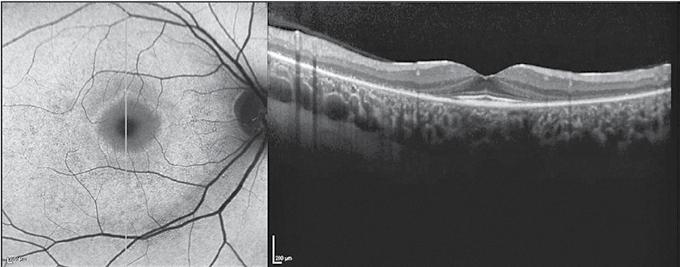

Se recomandă efectuarea unui examen oftalmologic complet înainte de începerea sau în primul an de tratament cu hidroxiclorochină. În cadrul acestui examen, pacienții ar trebui să facă o examinare a fundului de ochi; câmpurile vizuale (fig. 1) și tomografia de coerență optică (fig. 2) ar trebui să fie adăugate în cazul în care există maculopatie. Screeningul anual ar trebui să înceapă după 5 ani de utilizare a medicamentului pentru cei mai mulți pacienți, dar ar trebui să înceapă mai devreme la cei la care există factori de risc majori. Screeningul anual ar

Fig. 1: Modificare progresivă a perimetriei computerizate

Fig. 2: Modificări specifice la nivelul maculei vizibile în cadrul examenului OCT

Fig. 3: Apariția leziunilor maculare într-un interval de 3 ani după inițierea tratamentului cu hidroxiclorochină în urmă cu 10 ani